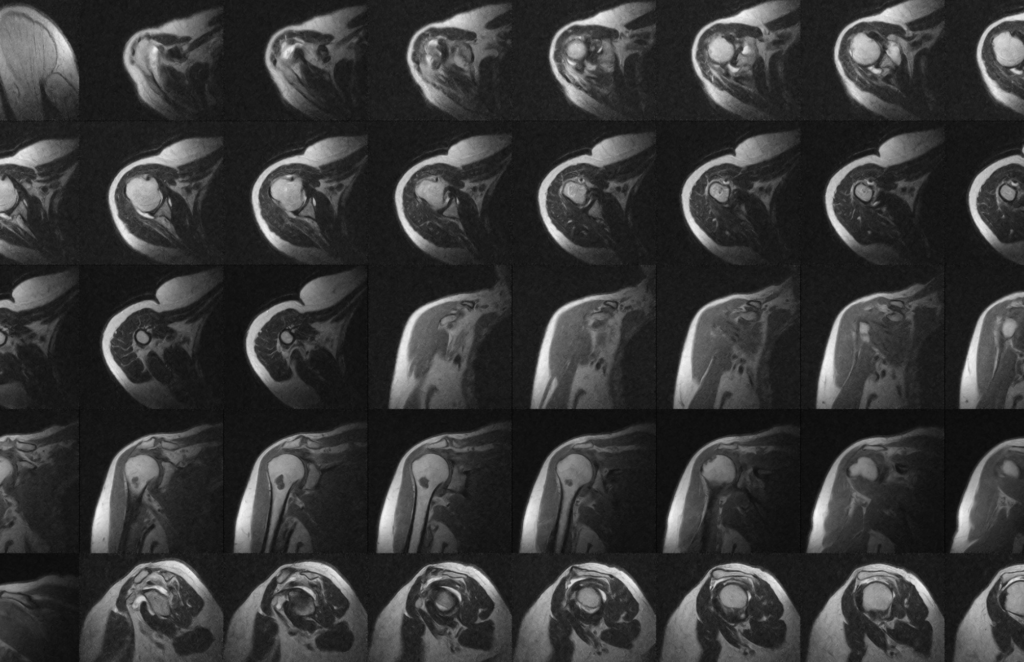

La diagnosi delle lesioni del sottospinato include una valutazione clinica dettagliata, che prevede l’esame dei sintomi del paziente, come dolore, debolezza e limitazione del movimento della spalla. Test specifici, come il test di Jobe o il test di rotazione esterna resistita, possono aiutare a identificare una lesione del sottospinato. L’imaging, come l’ecografia o la risonanza magnetica (RM), può fornire una conferma della diagnosi e determinare l’entità della lesione.